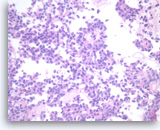

Pancreatic endocrine neoplasm #1,

Pancreas FNA, Direct Smear.

The aspirates show single and dyshesive clusters of neoplastic cells. The neoplastic cells show mild variation in size and have eccentrically located oval nuclei (plasmacytoid appearance). A few small cytoplasmic vacuoles are seen.

40X

Pancreatic endocrine neoplasm #1,

Pancreas FNA, Direct Smear.

The aspirates show single and dyshesive clusters of neoplastic cells. The neoplastic cells show mild variation in size and have eccentrically located oval nuclei (plasmacytoid appearance). A few small cytoplasmic vacuoles are seen.

40X